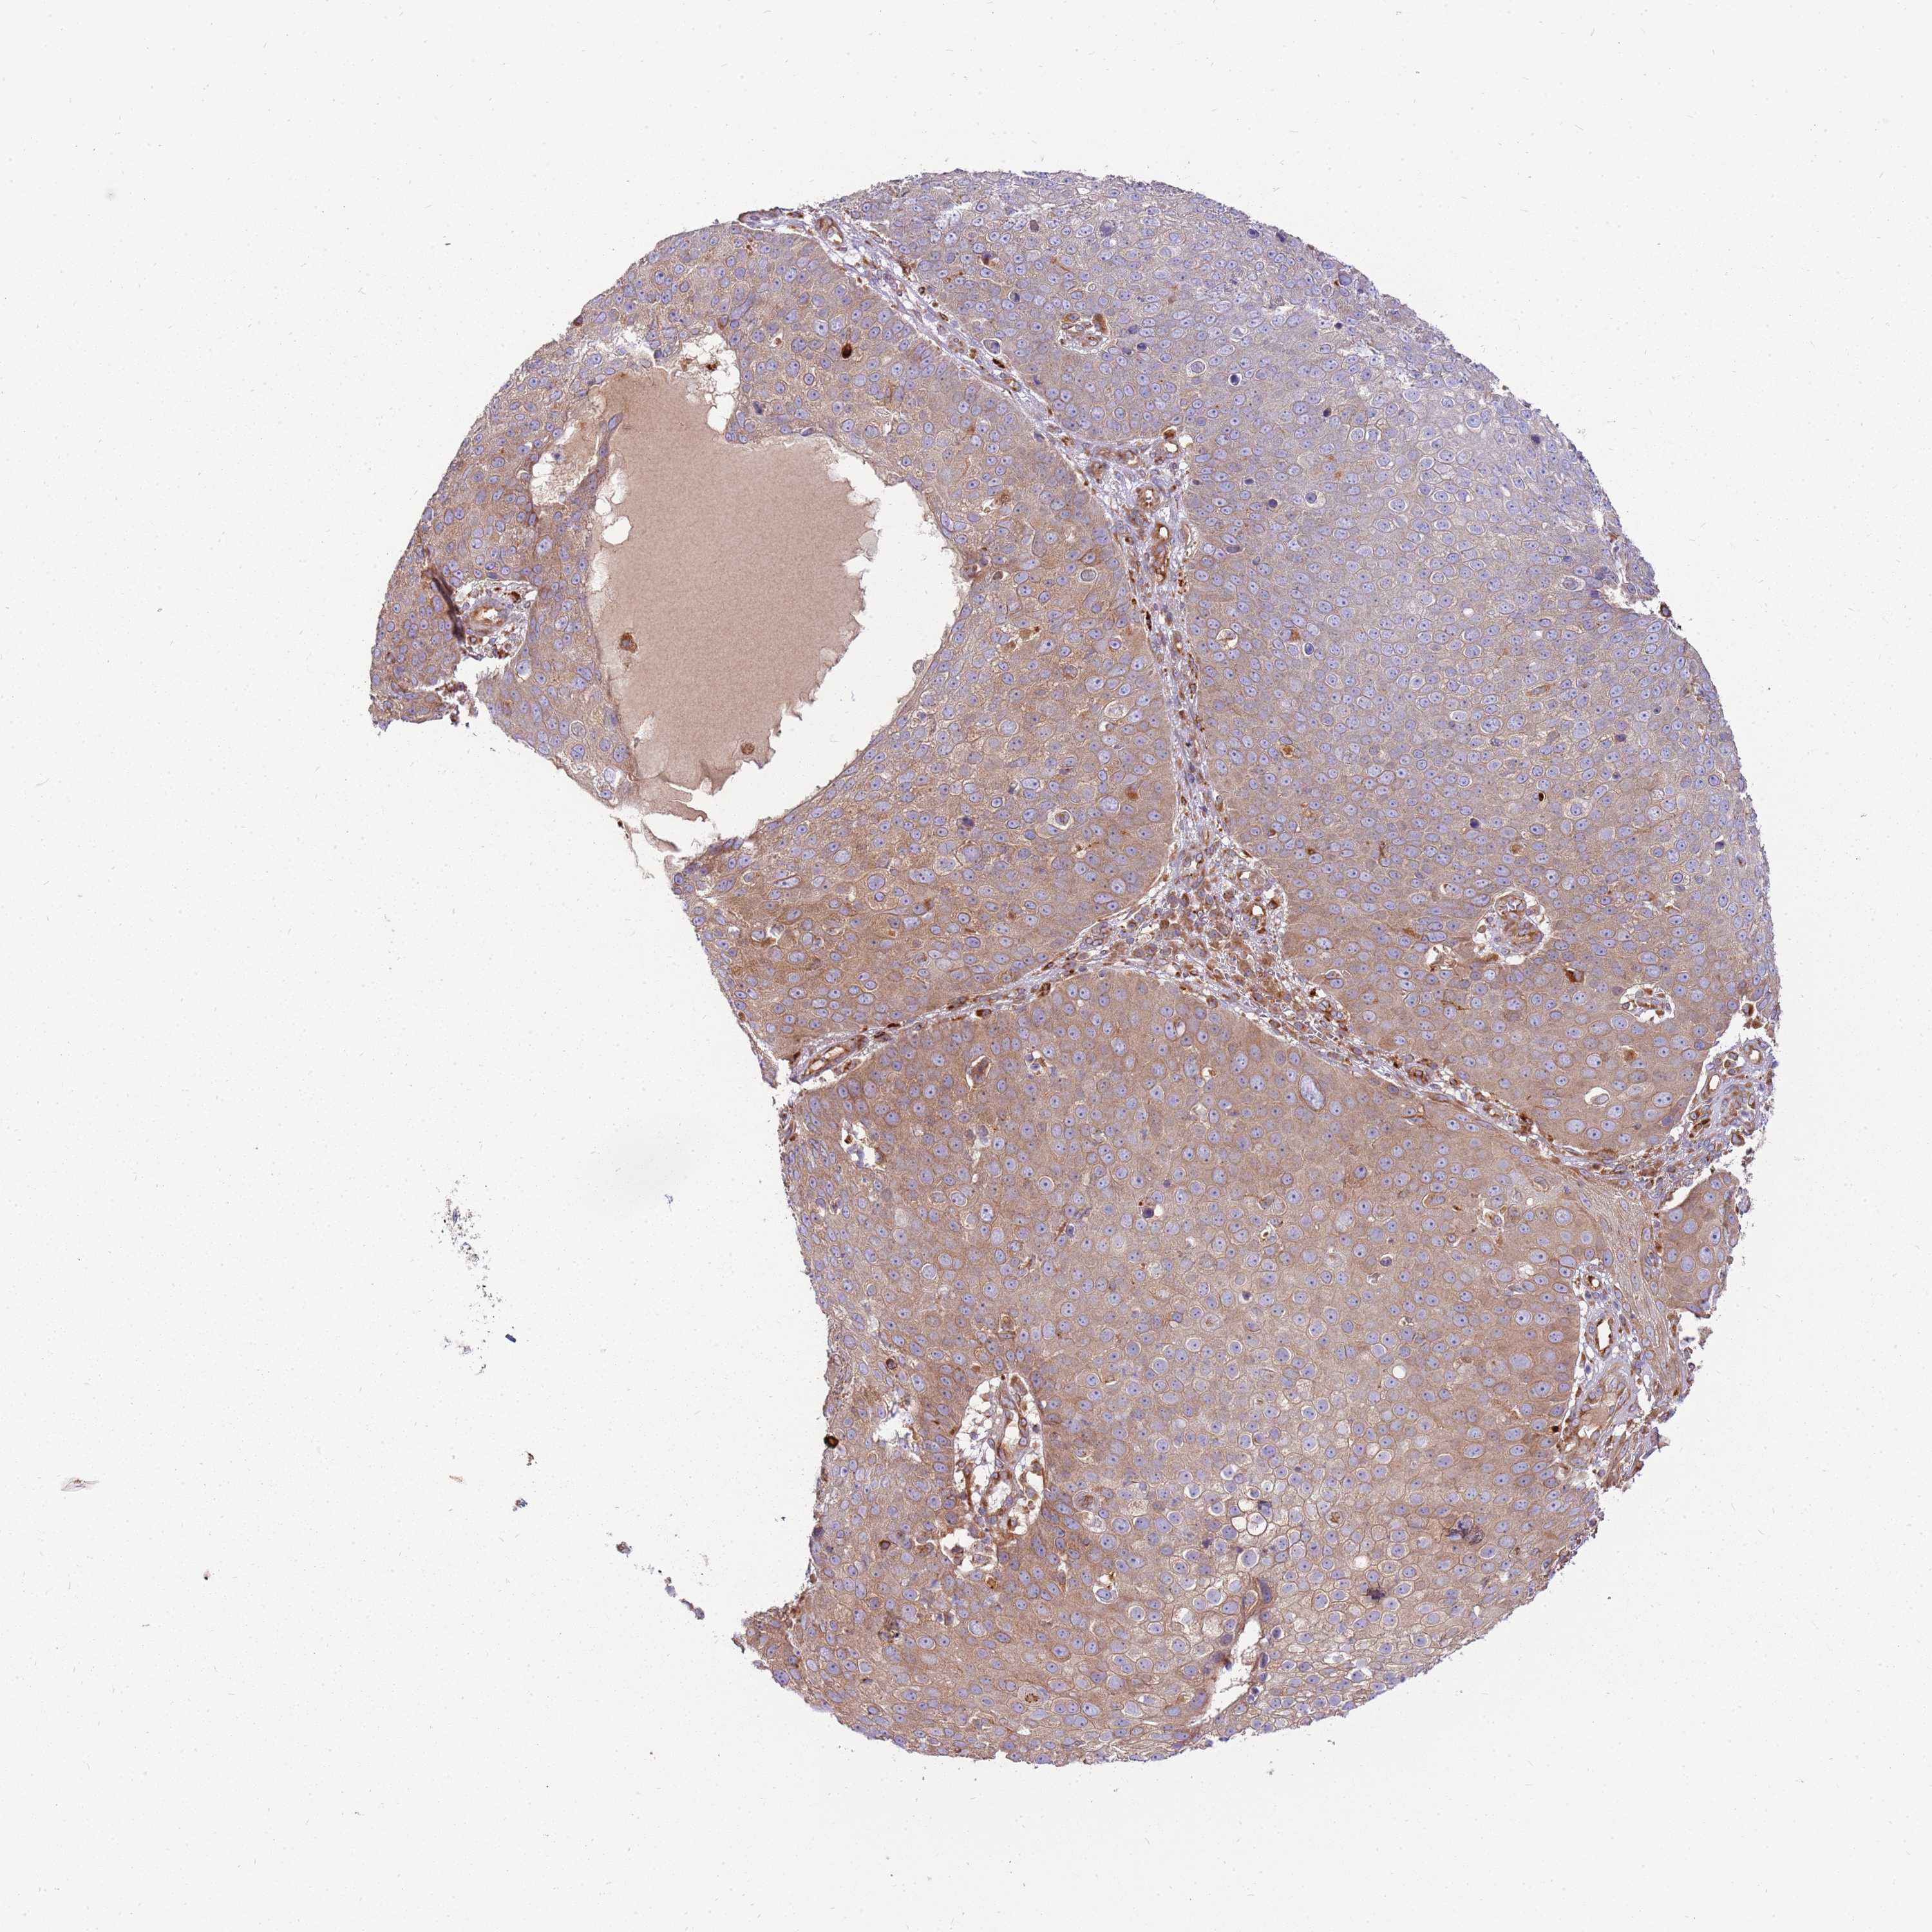

Basal cell and squamous cell cancer

SKIN CANCER - Protein expressioni

A mouse-over function shows sample information and annotation data. Click on an image to view it in a full screen mode. Samples can be filtered based on level of antibody staining by selecting one or several of the following categories: high, medium, low and not detected. The assay and annotation is described here.

Each image is clickable and will lead to virtual microscopy that enables deeper exploration of all samples and also displays staining intensity scores, fraction scores and subcellular localization as well as patient and tissue information for each sample.

Antibody HPA048904

Staining

High

Medium

Low

Not detected

Intensity

Strong

Moderate

Weak

Negative

Quantity

>75%

75%-25%

<25%

None

Location

Nuclear

Cytoplasmic/membranous

Cytoplasmic/membranous,nuclear

Basal cell carcinoma